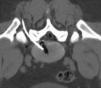

Durante el procedimiento se pidió al paciente que permaneciera en decúbito prono sobre la mesa del equipo de TC (fig. 1). Tras desinfectar la zona, se inyectó anestesia local con lidocaína mediante guía por TC en el punto de entrada de la aguja y a través de la fascia profunda y de las capas musculares (fig. 2). A continuación, y también mediante guía por TC usando el modo fluoroscopia de triple plano en tiempo real, se introdujo una aguja fina hueca de 18G con un estilete (COOK, William Cook Europe, Dinamarca) en el disco intervertebral, centrada en el núcleo pulposo, a medio camino entre las dos plataformas vertebrales, utilizando un abordaje posterolateral (fig. 3). El estilete se retiró y, tras comprobar su integridad, se introdujo dentro de la aguja una fibra óptica de 400μm esterilizada y con un tope proximal para evitar que la punta de la fibra protruyese más de 1,0cm de la punta de la aguja.